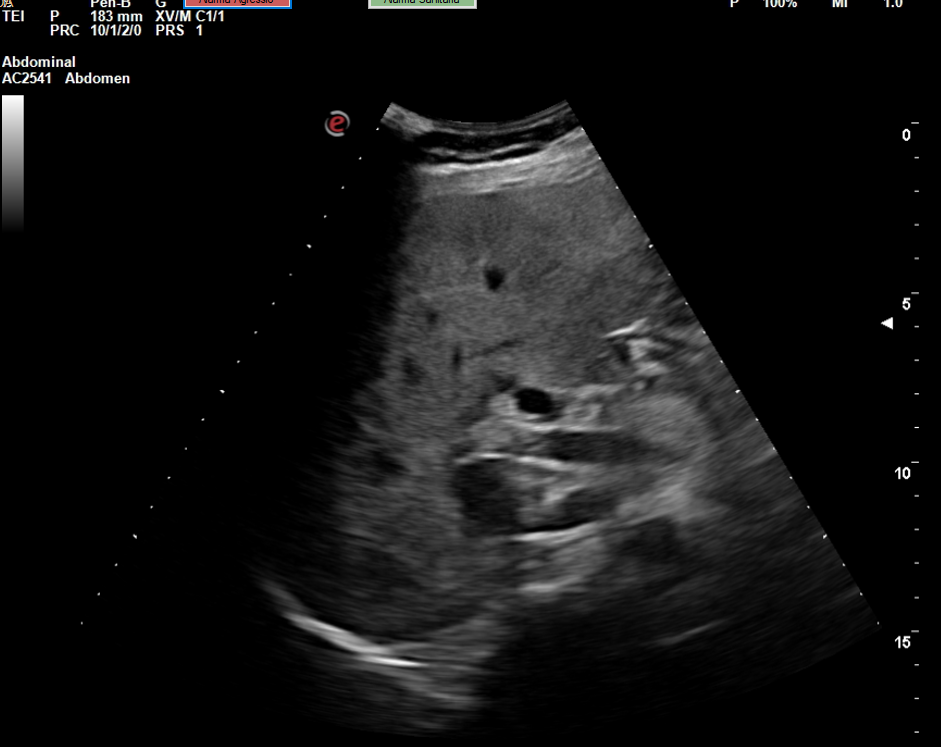

Descripción de los hallazgos ecográficos y las imágenes más relevantes para la resolución del caso

Se realiza la ecografía abdominal en el ambulatorio, donde se objetiva colelitiasis con el colédoco en el límite superior de la normalidad (4,4 mm), también presenta esteatosis hepática grado I. El resto de la ecografía no presenta hallazgos de interés.